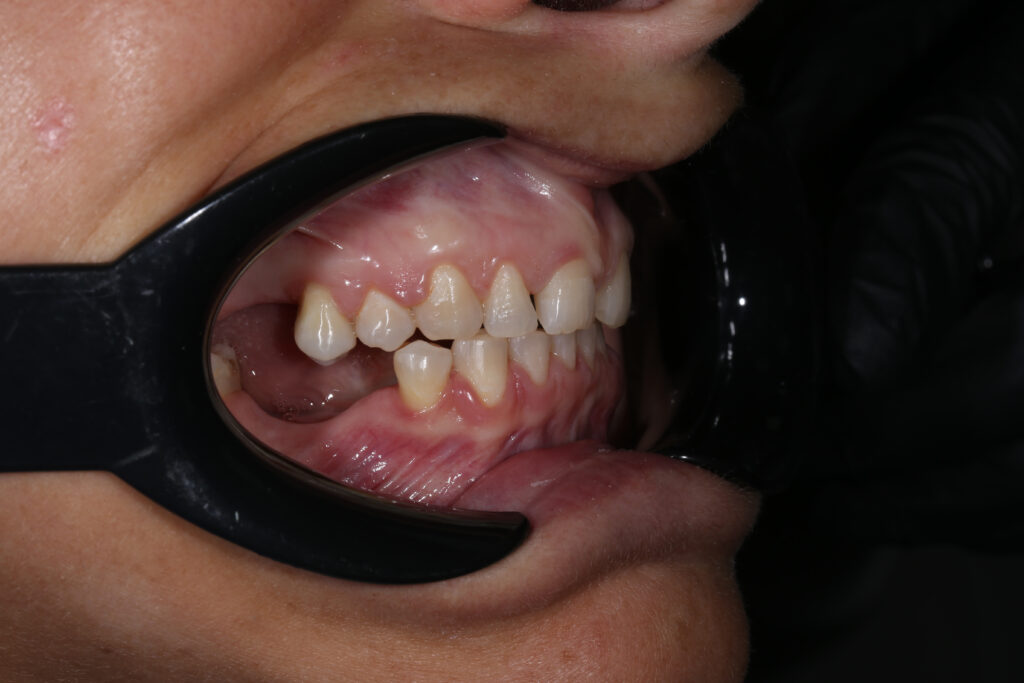

Ситуация до лечения

Пациент обратился за комплексным лечением.

Из-за множественных давних удалений жевательных зубов, произошла деформация зубных рядов, зубы разъехались в область удаленных, что затрудняло протезирование в момент обращения к ортопеду.

Так же можно отметить сильное снижение высоты прикуса (верхние зубы на 100% перекрывали нижние, что вызывало хроническую травму десны), а также повышенную стираемость твердых тканей зубов, что является следствием повышенной нагрузки, которую много лет испытывали передние зубы, в связи с отсутствием жевательных зубов.

В связи со всеми вышеперечисленными факторами, пациентка нуждалась в тотальной реабилитации.